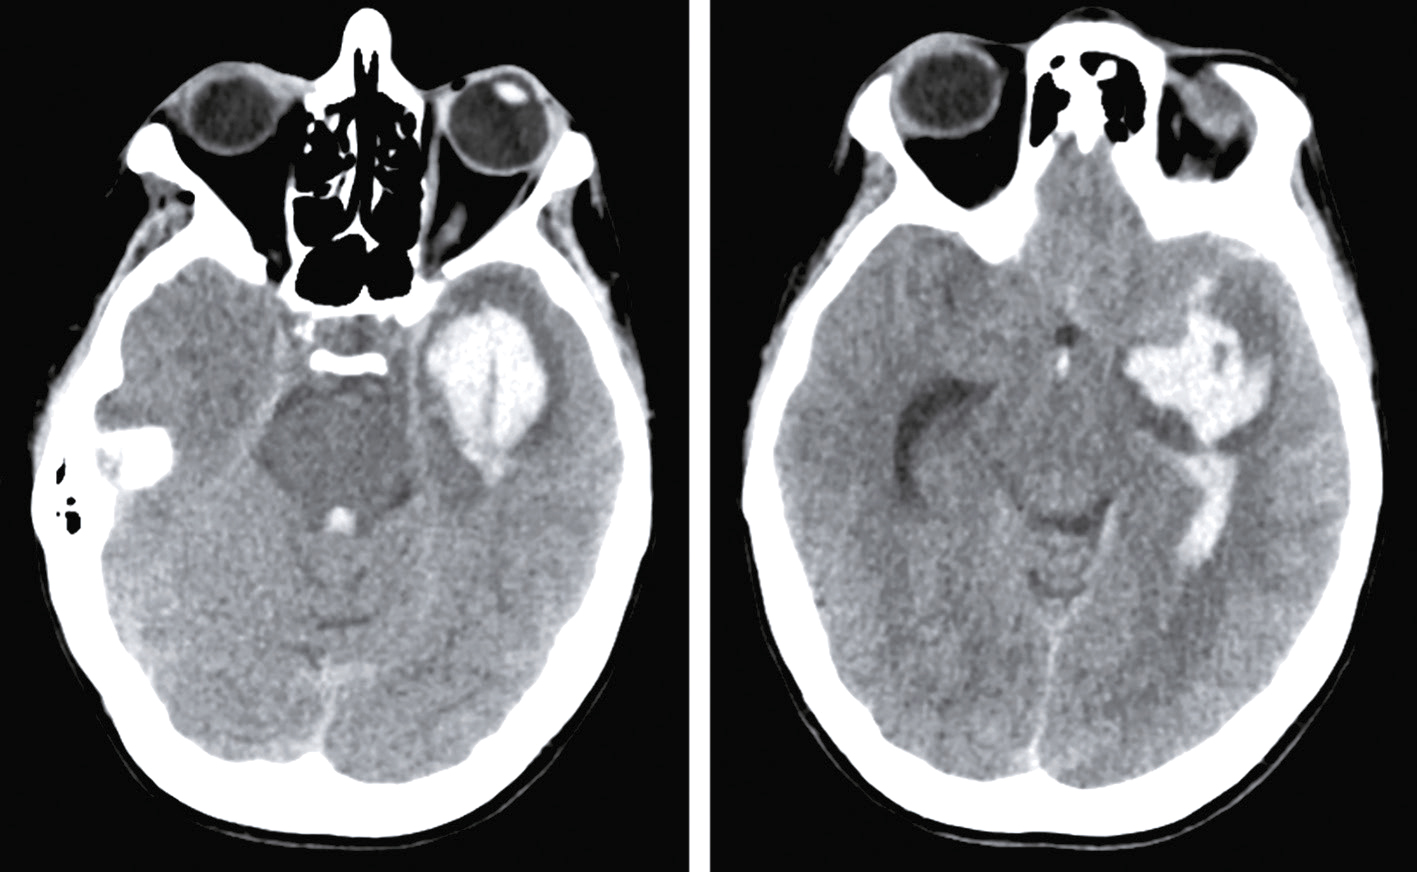

Une nouvelle IRM cérébrale est réalisée devant cette diplopie. Décrivez le cliché (fig. 31.1).

L'image montre une coupe transversale d'un cerveau humain obtenue par imagerie par résonance magnétique (IRM). Cette image est une vue axiale, ce qui signifie qu'elle est prise horizontalement à travers le cerveau. On peut observer les différentes structures cérébrales, y compris la matière grise et la matière blanche. Les ventricules latéraux, qui sont des cavités remplies de liquide céphalo-rachidien, sont visibles au centre de l'image. Les zones plus claires autour des ventricules peuvent indiquer des anomalies ou des lésions, souvent associées à des conditions neurologiques comme la sclérose en plaques. Les contours du cerveau sont bien définis, et les différentes régions du cortex cérébral sont clairement visibles. Cette image est intéressante car elle permet aux médecins de diagnostiquer et de surveiller diverses maladies neurologiques en visualisant les structures internes du cerveau avec une grande précision. L'IRM est une technique non invasive qui utilise des champs magnétiques et des ondes radio pour produire des images détaillées des organes et des tissus internes, ce qui est crucial pour la détection précoce et le traitement des maladies cérébrales.

- A coupe sagittale

- B séquence T1

- C hypersignaux de la substance blanche périventricu-laire

- D hypersignaux du tronc cérébral

- E hypersignaux juxtacorticaux